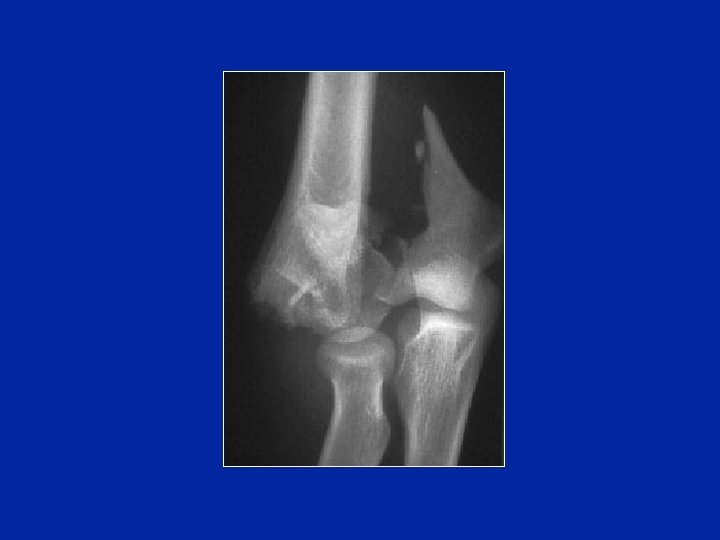

Condilo esterno

Fratture del condilo esterno

(fr di Kocher)